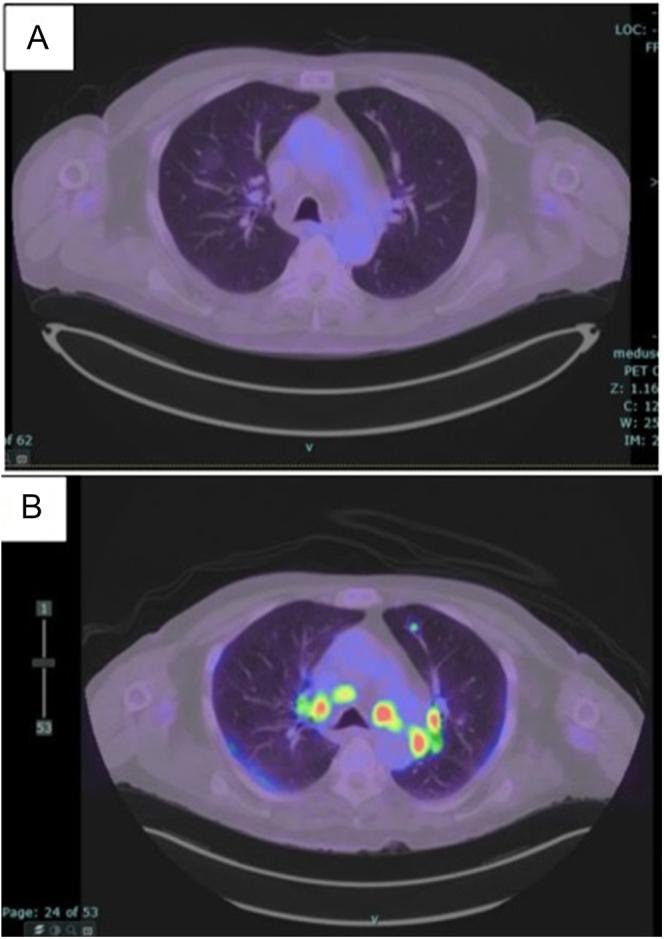

Summary: We presented a case of a 72-year-old male with severe hypercalcaemia of 3.84 mmol/L following the second cycle of immunotherapy with ipilimumab and nivolumab in the setting of metastatic melanoma with known bone metastases. Further investigations demonstrated hilar lymphadenopathy, which was not present in previous imaging, and subsequent hypercalcaemia work-up demonstrated a significantly elevated serum calcitriol level as high as 429 pmol/L. A diagnosis of drug-induced sarcoid-like reactions or DISRs was made on the basis of hypercalcaemia and hilar lymphadenopathy following immunotherapy. Hypercalcaemia was effectively treated with intravenous fluids and medical therapy including a short course of subcutaneous calcitonin, a total of 120 mg of denosumab and oral prednisolone.

Learning points: DISRs are a rare complication of immunotherapy and may mimic metastases. A temporal relationship between commencement of therapy and progression on clinical imaging is important in making an accurate diagnosis.Calcitriol-mediated hypercalcaemia secondary to DISRs is an important differential diagnosis to hypercalcaemia of malignancy and should be considered in patients who have undergone immunotherapy.Prednisolone should be considered as the next line of treatment after fluid therapy in patients with calcitriol-mediated hypercalcaemia. Prednisolone and denosumab both reach maximum clinical efficacy between 7 and 10 days. Therefore, treatment administration should be spaced out by at least five days to avoid iatrogenic hypocalcaemia.